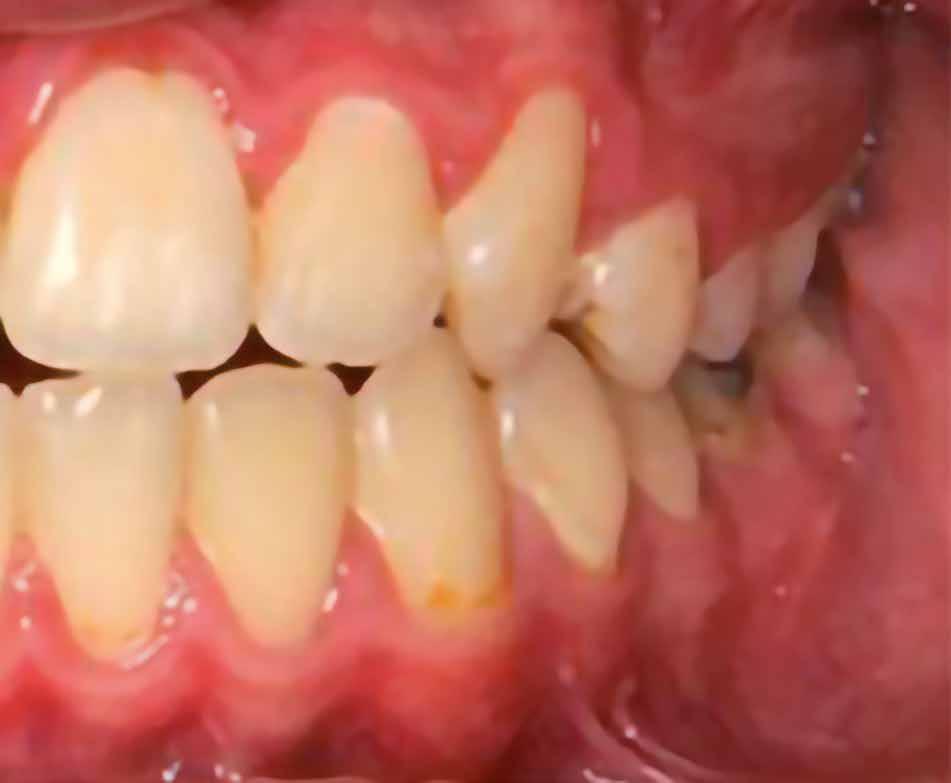

A 10 éves férfi páciens a felső frontfogai késői/nem megvalósuló előtörése miatt kereste fel a rendelőnket. A klinikai és a radiológiai vizsgálat során a jobb felső nagymetszőfog impakcióját észleltük (1. ábra). A fog horizontális tengelyállással és dilacerált gyökérrel rendelkezett. A felső dentális középvonal a fogak vándorlása miatt jelentős mértékben elcsúszott. A bal felső kismetszőfog is rendkívül kedvezőtlen pozícióba került.

Dr. Kazem Dalaie, dr. Samin Ghaffari, dr. Mazir Mir (Irán, Németország) 1. a ábra: Az intraorális felvételen jól látható a jobb felső nagymetszőfog lehetséges impakciójára utaló foghiány.

1. b ábra: A panoráma röntgenfelvételen megfigyelhető a teljes impakcióban lévő jobb felső nagymetszőfog. 1. c ábra: A CBCT felvétel is igazolja a jobb felső nagymetszőfog impakcióját.

2. ábra: Az impaktált fog lézerrel asszisztált sebészi feltárása. 3. ábra: A kezelés megkezdését követő 15. hónapban megfigyelhető a sikeres felszabadítást, fogmozgatást és pozicionálást követően látható állapot.